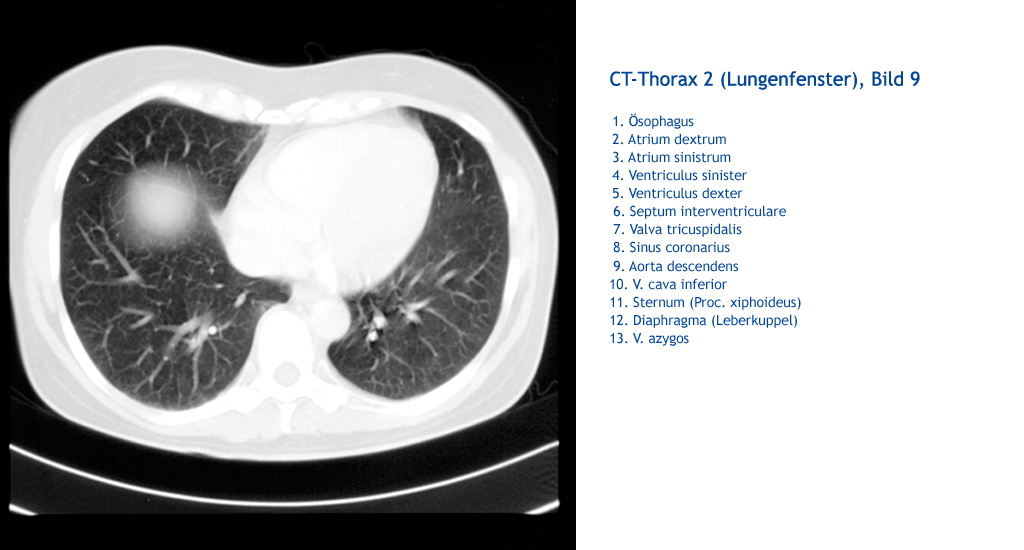

V. azygos Diaphragma (Leberkuppel) Sternum (Proc. xiphoideus) V. cava inferior Aorta descendens Sinus coronarius Valva tricuspidalis Septum interventriculare Ventriculus dexter Ventriculus sinister Atrium sinistrum Atrium dextrum Ösophagus